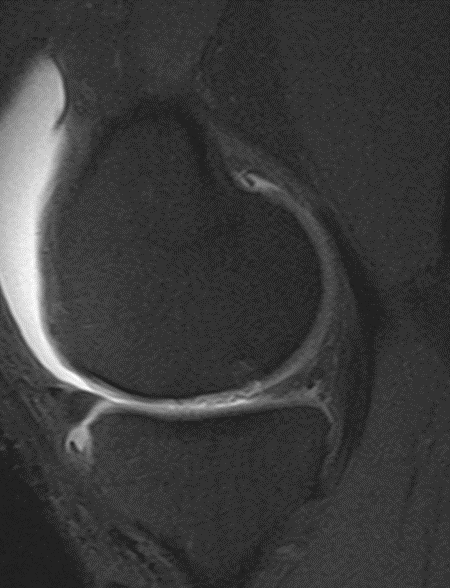

Four months after cartiform to femoral condyle